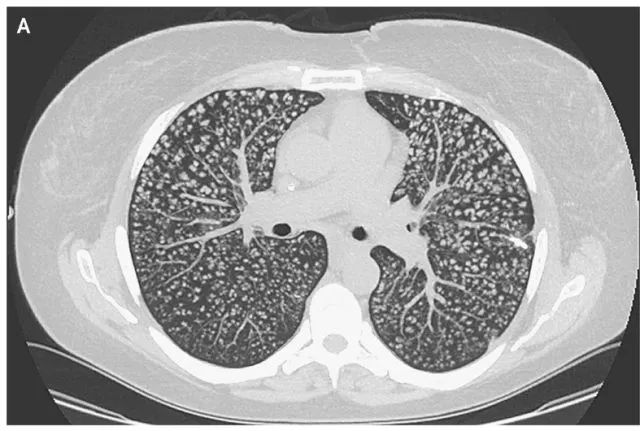

影像学检查:胸部CT显示双侧肺部弥漫性多发性小叶中央型高密度结节(下图所示)。

图 A胸部CT显示双侧肺部弥漫性小叶中央型高密度结节